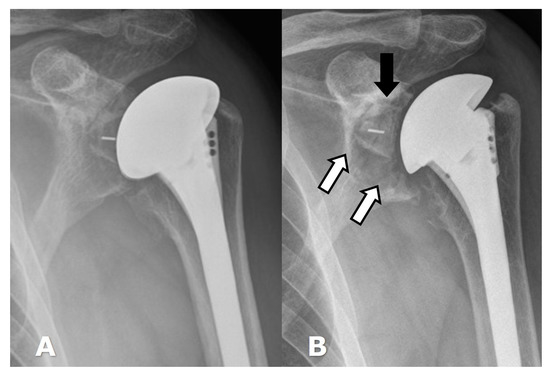

5.2. Reverse Arthroplasty

Reverse Total Shoulder Arthroplasty (RTSA)

|---|---|

| 1 | Lucency extends to scapular pillar |

| 2 | Lucency contacts the inferior glenoid screw |

| 3 | Lucency extends over the inferior glenoid screw |

| 4 | Lucency extends under the metaglene/baseplate |